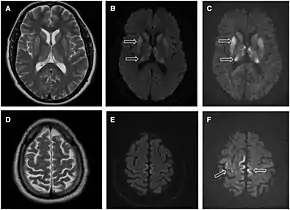

Through the image of MRI, the obvious precipitation of prion protein in the brain is visible.

• MRI of the brain – often shows high signal intensity in the caudate nucleus and putamen bilaterally on T2-weighted images.

Imaging

Imaging of the brain may be performed during medical evaluation, both to rule out other causes and to obtain supportive evidence for diagnosis. Imaging findings are variable in their appearance, and also variable in sensitivity and specificity.[43] While imaging plays a lesser role in diagnosis of CJD,[44] characteristic findings on brain MRI in some cases may precede onset of clinical manifestations.[45]

Brain MRI is the most useful imaging modality for changes related to CJD. Of the MRI sequences, diffuse-weighted imaging sequences are most sensitive.[46] Characteristic findings are as follows:

dwMRI, FDG PET and post mortem histology from a patient who presented with sCJD aged 66

• Focal or diffuse diffusion-restriction involving the cerebral cortex and/or basal ganglia. In about 24% of cases DWI shows only cortical hyperintensity; in 68%, cortical and subcortical abnormalities; and in 5%, only subcortical anomalies.[47] The most iconic and striking cortical abnormality has been called "cortical ribboning" or "cortical ribbon sign" due to hyperintensities resembling ribbons appearing in the cortex on MRI.[48] The involvement of the thalamus can be found in sCJD, is even stronger and constant in vCJD.[49]

• Varying degree of symmetric T2 hyperintense signal changes in the basal ganglia (i.e., caudate and putamen), and to a lesser extent globus pallidus and occipital cortex.[44]

• Cerebellar atrophy

Brain FDG PET-CT tends to be markedly abnormal, and is increasingly used in the investigation of dementias.

• Patients with CJD will normally have hypometabolism on FDG PET.[50]